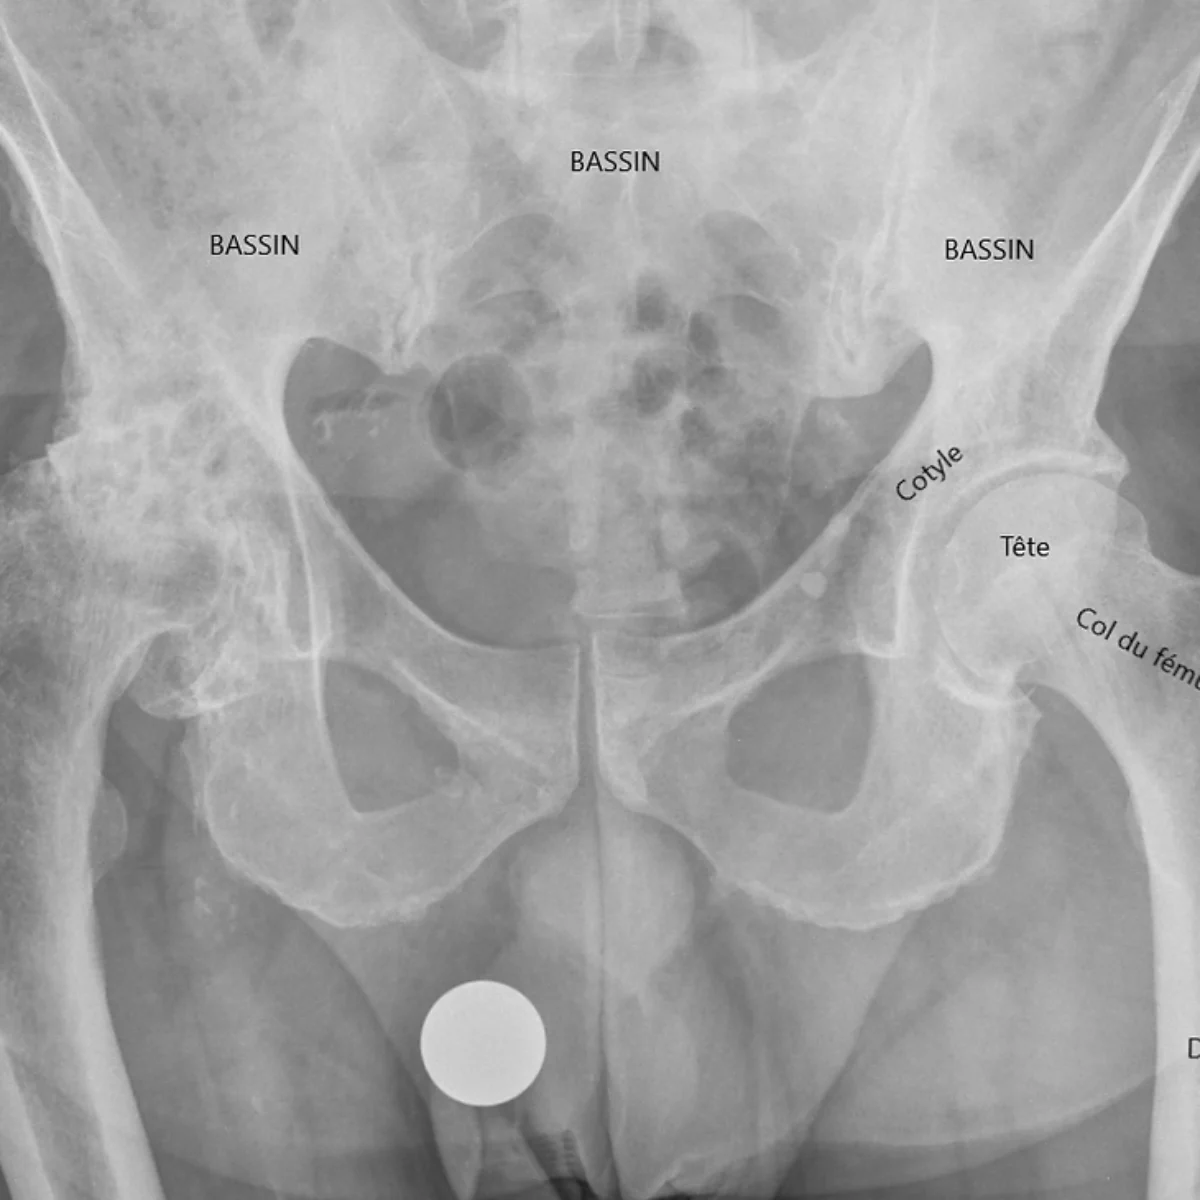

Information complète à destination des patients Cette page d’information médicale a pour objectif de vous expliquer de façon claire, détaillée et accessible ce qu’est l’ostéotomie périacétabulaire (OPA). Vous y trouverez des explications sur l’anatomie de la hanche, la dysplasie, les raisons pour lesquelles une ostéotomie peut être proposée, la préparation à l’intervention, le déroulement précis de l’opération, les suites post-opératoires,...